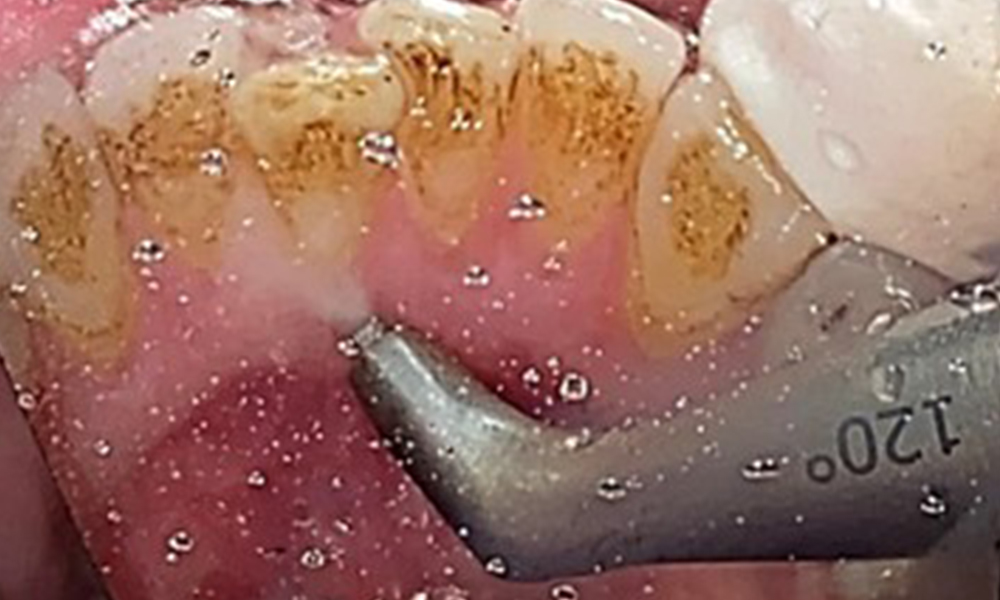

Close-up view of teeth

Fig. 5: Close-up view of teeth 45 to 47. The green arrows show dental attrition and erosions of the buccal cusps with partial enamel loss, © Dr R. Krapf

The patient has full dentition with a total of 28 teeth. There were noteworthy erosions and attritions. (Fig. 4, Fig. 5). Due to bruxism, the patient has been wearing a splint with an adjusted bite block at night for many years. The erosions were caused by long-term consumption of isotonic beverages. No periodontal bone loss or active caries were observed.

Due to the otherwise favourable general medical condition, the needs determined during the intraoral examination will be decisive for their treatment. It will be essential to periodically determine the probing depths. Gingival bleeding decreases in smokers, which is why the clinical diagnosis of periodontitis can only be made by probing (Fig. 7). Placing exclusive focus on the determination of bleeding indices may obscure existing periodontitis or gingivitis. (5)